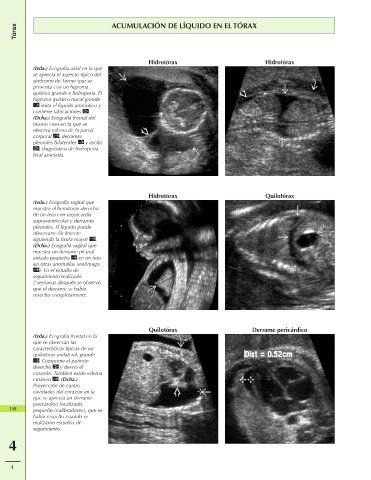

Tórax ACUMULACIÓN DE LÍQUIDO EN EL TÓRAX

Hidrotórax Hidrotórax

(Izda.) Ecografía axial en la que

se aprecia el aspecto típico del

síndrome de Turner que se

presenta con un higroma

quístico grande e hidropesía. El

higroma quístico nucal grande

imita el líquido amniótico y

contiene tabicaciones .

(Dcha.) Ecografía frontal del

mismo caso en la que se

observa edema de la pared

corporal , derrames

pleurales bilaterales y ascitis

, diagnóstico de hidropesía

fetal asociada.

Hidrotórax Quilotórax

(Izda.) Ecografía sagital que

muestra el hemitórax derecho

de un feto con taquicardia

supraventricular y derrames

pleurales. El líquido puede

observarse fácilmente

siguiendo la fisura mayor .

(Dcha.) Ecografía sagital que

muestra un derrame pleural

aislado pequeño en un feto

sin otras anomalías (estómago

). En el estudio de

seguimiento realizado

2 semanas después se observó

que el derrame se había

resuelto completamente.

Quilotórax Derrame pericárdico

(Izda.) Ecografía frontal en la

que se observan las

características típicas de un

quilotórax unilateral, grande

. Comprime el pulmón

derecho y desvía el

corazón. También existe edema

cutáneo . (Dcha.)

Proyección de cuatro

cavidades del corazón en la

que se aprecia un derrame

pericárdico localizado,

158 pequeño (calibradores), que se

había resuelto cuando se

realizaron estudios de

seguimiento.